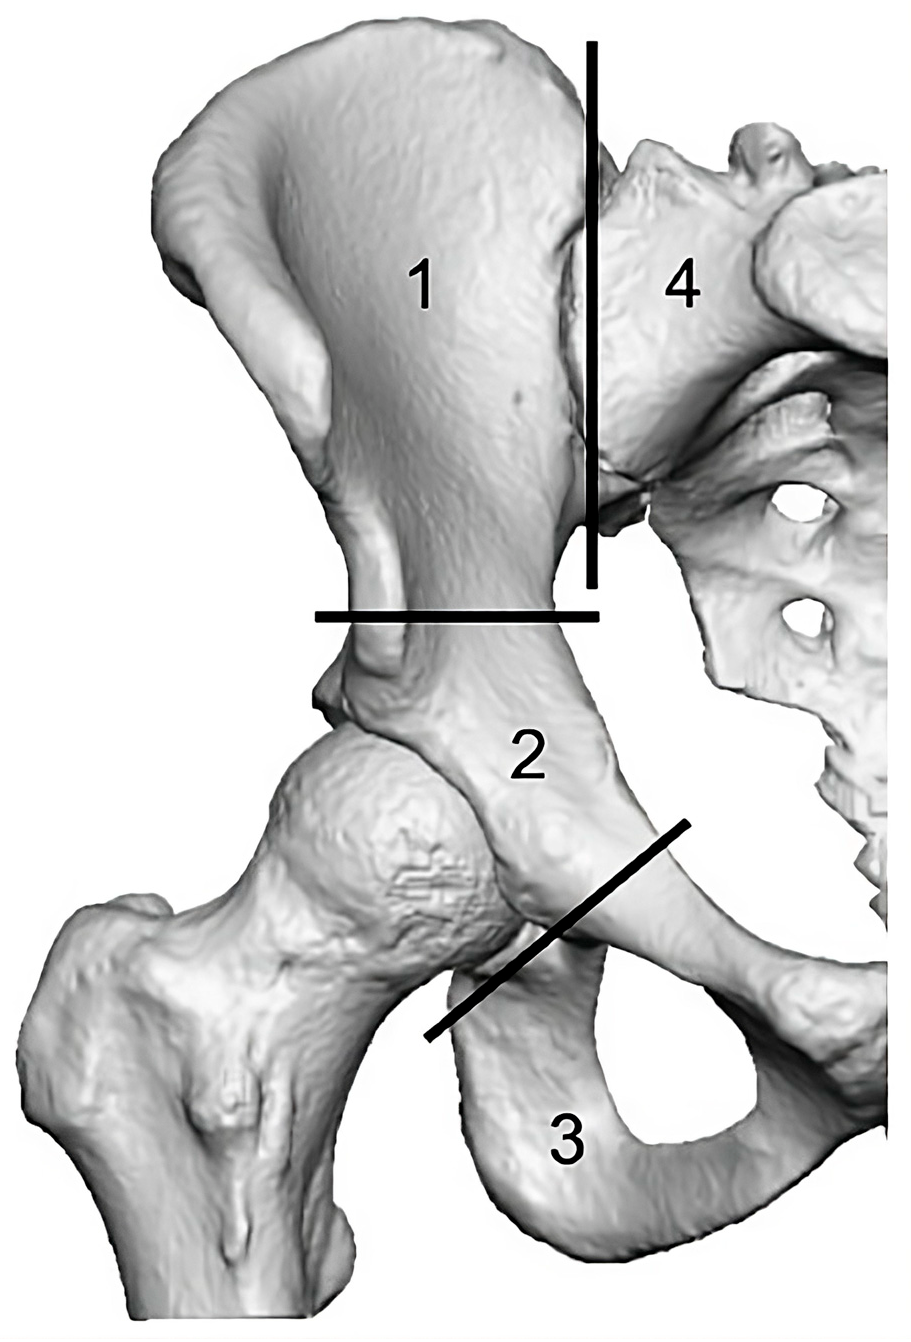

Patients with pelvis bone tumors were operated at the Rizzoli Orthopedic Institute. They all underwent massive hip reconstruction, including a type 2 tumor resection (Figure 1), as per Enneking’s classification of pelvic resections [55]. They all shared the need for the complete reconstruction of the hip joint. A total of 17 patients were randomly divided into two groups; one patient was excluded for low-resolution post-operation CT scans (slice thickness > 2 mm) which prevented the 3D-model reconstruction for subsequent analysis. This is because the CT scans for that patient were carried out using settings for clinical assessment at the 6 month follow-up rather than for morphological analysis. Future scans intended for morphological analysis must adhere to the required scan settings. Ultimately, eight patients (female/male: 4/4; age: 32.2 ± 8.0; Body Mass Index: 22.0 ± 3.0 kg/m2) had received a customized 3D-printed implant, and the other eight patients (female/male: 3/5; age: 42.8 ± 9.8; Body Mass Index: 21.0 ± 3.2 kg/m2) received bone grafts in combination with standard off-the-shelf acetabular and femoral components (CLS stem/acetabular component, Zimmer GmbH, Winterthur, Switzerland). The second group represents the conventional procedure for these clinical cases, and thus serves as a benchmark for 3D-printed custom implants.

Figure 1. Enneking’s tumor resection classification [22].